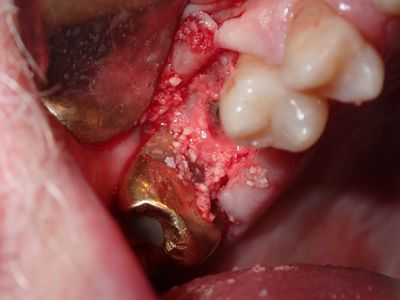

NSankhyan - 16, 26 sinus lift

16 - previous graft and fistula, softer bone, apical bone is into sinus chamber, no perforation of membrane, packed bone, implant placed